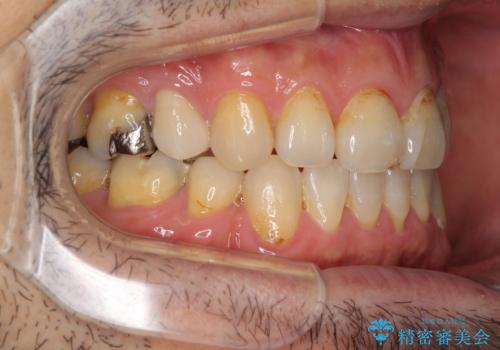

- むし歯による奥歯の痛みを気にして来院された患者様です。

神経にまでむし歯の及んでいる歯や、既に根管治療がされている歯に痛みがあったため、まずは根管治療を行うこととしました。

その後、以前行った抜歯矯正の後戻りをインビザライン・ライトにより改善し、むし歯や銀歯はオールセラミッククラウンにて補綴治療することとしました。